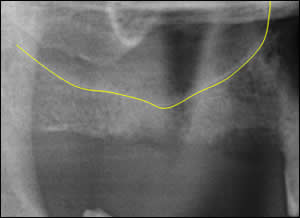

Fig 2: Tracing of the sinus floor